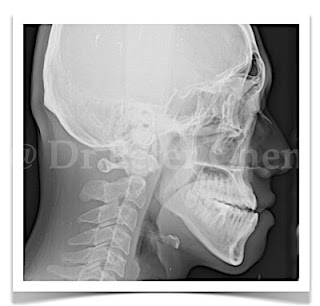

前幾天收到一個病人的信,問我有關正顎手術的問題。信中提到不知道自己是否需要手術,因為情況比較特殊,下排牙齒在上排牙齒前面,但下巴看起來是後縮的,他擔心如果做手術把牙齒推進去,下巴不是更縮更醜了?

其實這種情況並不少見,下顎骨牙床部分前凸,往下到頦骨時向後傾斜,外觀上就會形成下排牙齒在前,但下巴縮在後面,手術設計上,可以將下顎骨後退,合併下巴手術將頦骨(下巴骨)前移,就可以同時改善這兩個問題。

療程效果因人而異,上圖為該案例實際術後成效